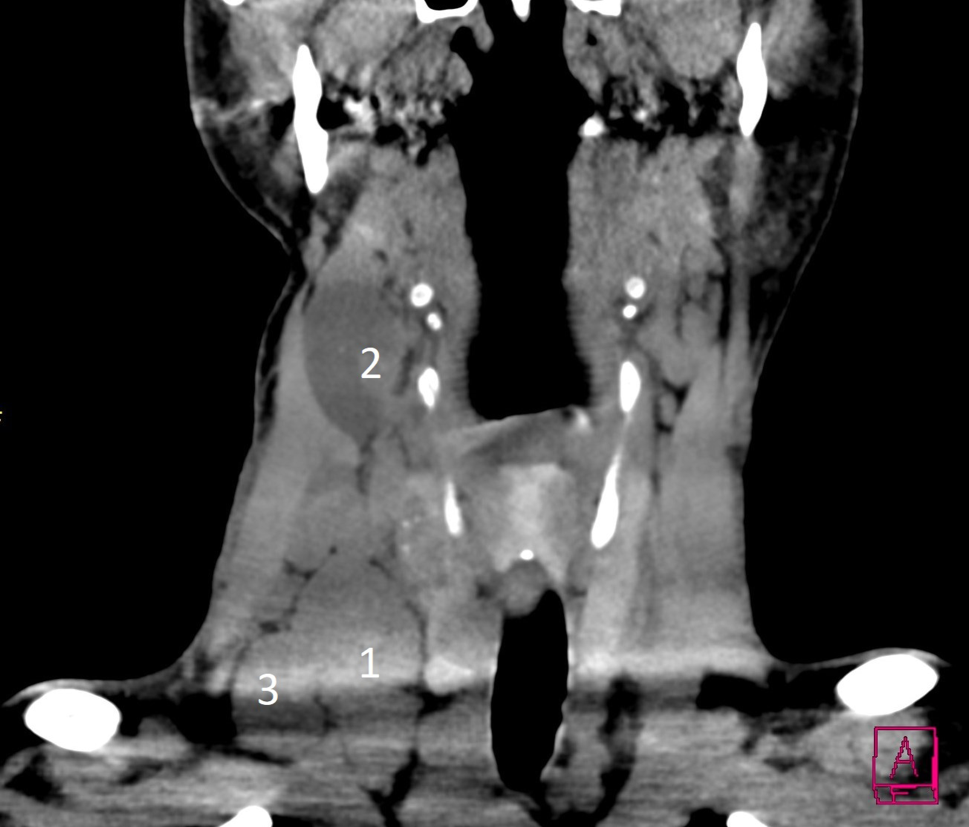

Abb. 4

CT ohne Kontrastmittel mit ausgedehnter Lymphknotenmetastasierung im lateralen rechten Hals (1 = Level IV Lnn, 2 = Level III Lnn, 3 = Level V Lnn)

Die Ultraschalldiagnostik für Schilddrüse, Lymphknoten und Nebenschilddrüsen sollte demnach idealerweise auch vom Chirurgen beherrscht werden. Ein positiver Lymphknotennachweis im lateralen Kompartment (Regio IV, V, III, II – einen Überblick zeigt das CT in Abb. 4) lässt dann schon präoperativ eine laterale Halsdissektion einplanen (OP Bild Abb. 5), was sowohl für den Zugangsweg, die geplante Länge der Operation und auch die Wahl des spezialisierten Chirurgen von wesentlicher Bedeutung ist. Schwierig ist speziell die sonographische Lymphknotendiagnostik im zentralen Kompartment (Regio VI) bzw. im oberen mediastinalen Kompartment (Regio VII), die bei routinemäßiger Ultraschalluntersuchung durch Radiologen und Nuklearmediziner nicht immer erfasst wird. Anzumerken ist auch, dass retrotracheale, paraösophageale und vor allem sogenannte retrorecurrente (dorsal des N. laryngeus recurrens) Lymphknoten oft mit der Sonographie nicht einsehbar sind (Abb. 6; [1517]).